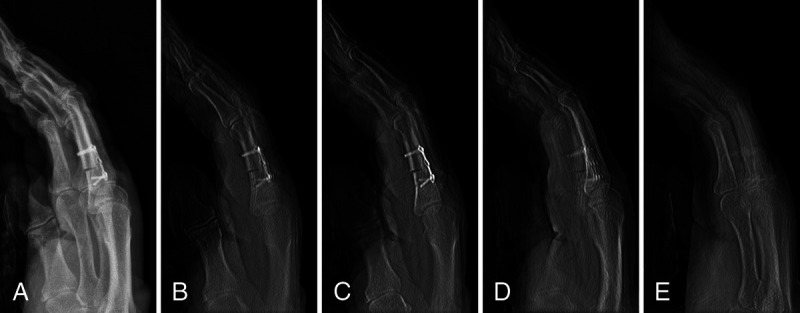

Materials and methods: After surgical fracture induction and subsequent osteosynthesis, 8 cadaveric fracture models (wrist, metacarpus, ankle, metatarsus) were scanned with the prototypical tomosynthesis mode of a multiuse x-ray system. Tomosynthesis protocols at 60, 80, and 116 kV (sweep angle 10°, 13 FPS) were compared with standard radiograms. Five radiologists independently rated diagnostic assessability based on an equidistant 7-point scale focusing on fracture delineation, intra-articular screw placement, and implant positioning. The intraclass correlation coefficient (ICC) was calculated to analyze interrater agreement.

Abstract Image